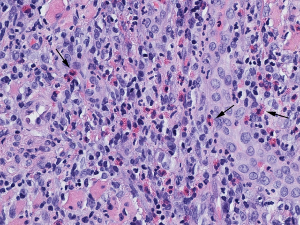

Histopathology reveals dense mixed inflammatory infiltrate of lymphocytes, plasma cells, large mononuclear cells include histiocytes and numerous eosinophils (Figure 3).